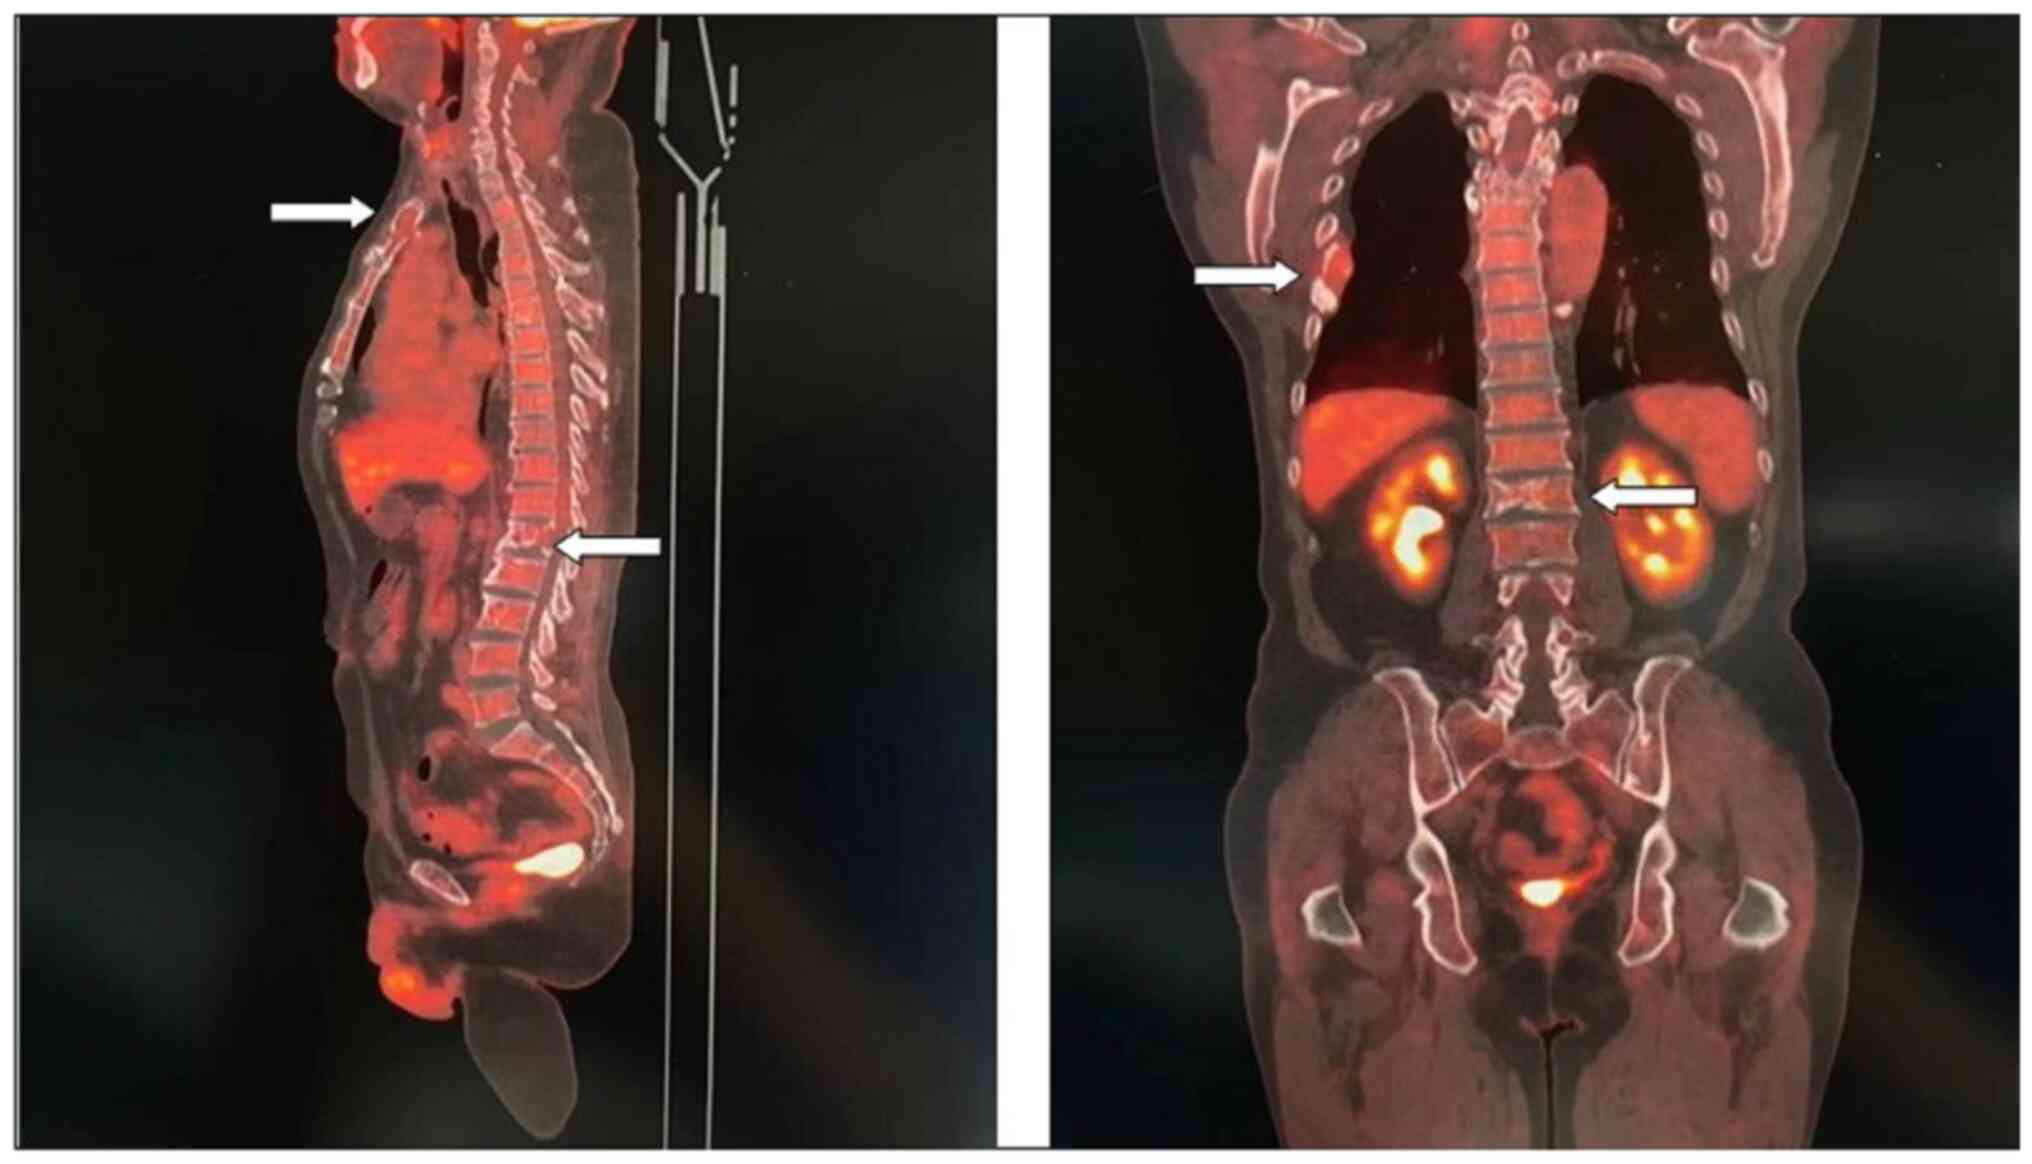

Subsequently, the patient presented with a lump around the colostomy stoma site and intermittent abdominal pain in November 2020. Physical examination revealed a lump measuring ~10×10 cm around the stoma, which did not reduce in size when the patient was lying flat. Abdominal CT (Fig. 4) revealed that the intestinal tube had protruded into the subcutaneous fat layer of the abdomen. Based on the patient's medical history, physical examination (a lump around the colostomy stoma site) and the result of abdominal CT (Fig. 4), a parastomal hernia was suspected. Surgery was the recommended treatment. Routine preoperative blood tests, coagulation function, and liver and kidney functions showed no abnormalities. Parastomal hernia repair surgery was performed using the keyhole technique in November 2020. A relatively soft drainage tube was placed subcutaneously in the surgical area. The patient recovered well after the surgery and was discharged on the third postoperative day without removing the drainage tube. During discharge, the surgical area was not compressed. However, five days after discharge, the patient experienced swelling, pain and bleeding at the surgical site. Abdominal CT showed a hematoma in the surgical area (Fig. 5). After taking hemostatic treatment measures (hemostatic drugs, compression hemostasis), fresh blood still slowly flowed out from the drainage tube. Dynamic reexamination of coagulation function showed that it gradually deteriorated, and the activated partial thromboplastin time was gradually delayed to 60 sec, which was 20 sec longer than normal (reference range, 20–40 sec). The patient had stubborn anemia, and after multiple blood transfusions, no significant increase was identified in hemoglobin, which remained between 45–68 g/l (normal range, 130–175 g/l). A bone marrow biopsy was also performed to investigate the cause of persistent bleeding (Fig. 6). The bone marrow smear was stained using the Wright staining method and 200 cells were counted under a microscope. The results showed abnormal proliferation of plasma cell lines in bone marrow smears, accounting for 35% of total cells, with an immature plasma cell composition accounting for 21.0% of total cells (normal range, 0–0.8%). This result is consistent with the diagnosis of multiple myeloma (10,11). Fig. 6 shows the characteristics of abnormal plasma cells: This type of cell was significantly different in size, with the cell body and nucleus appearing circular, elliptical, ovoid or irregular in shape. The nucleus was misaligned, the chromatin of the nucleus appeared as a granular or loose network and certain cells showed obvious nucleoli. The cytoplasm was rich, stained opaque dark blue and flame-like, with obvious light staining bands around the nucleus. Nodular protrusions and vacuoles were easily observed, while no particles were seen. The morphological features were consistent with those of MM (10). Further testing revealed elevated serum immunoglobulin A (IgA) levels of 76.7 g/l (normal range, 0.82–4.53 g/l) and significantly increased serum β2 microglobulin (β2-microglobulin) levels of 16,205 ng/ml (normal range, 604–2,286 ng/ml). Based on the results of the bone marrow puncture, the bone destruction, anemia and bleeding were attributed to MM. After consultation with a hematologist, the patient was diagnosed with MM (IgA-λ type, Durie-Salmon Stage III). The Durie-Salmon staging system is a classic staging system for MM. The staging criteria for Stage III are as follows: One or more of the following abnormalities must be present: Hemoglobin <8.5 g/dl; serum calcium >12 mg/dl; very high myeloma protein production; IgG peak >7 g/dl; IgA peak >5 g/dl; Bence Jones protein >12 g/24 h; and >3 lytic lesions on bone survey (11). The patient was transferred to the hematology department and was treated with the PCD regimen (bortezomib, cyclophosphamide, dexamethasone), chemotherapy and blood transfusion. The specific dosage of medication is calculated based on the patient's body surface area. One chemotherapy cycle is 4 weeks and this patient received 6 cycles of chemotherapy. Afterwards, the patient received maintenance treatment with bortezomib monotherapy. The seventh rib lesion invaded the surrounding soft tissue, and the interventional department performed an empty needle puncture biopsy on it. The pathological and immunohistochemical results of the puncture tissue are consistent with multiple myeloma (10). The lesion was determined to be plasmacytoma, suggesting involvement of MM (Fig. 7), and the immunohistochemical results were as follows: CD138 (+), CD38 (+), cytokeratin (CK) (−), Ki67 (15%, +), Lambda (+) and MM oncogene 1 (+) (Fig. 8). CK negativity indicated the absence of malignant cells of epithelial origin. The patient's condition gradually improved, with increasing hemoglobin levels, recovering coagulation function, absorption of the hematoma around the stoma (Fig. 9) and alleviation of bone pain. For the past 2 years, the patient has been regularly treated in the hematology department and the progression of the MM has been slow (Figs. 10 and 11). Fig. 10 is a PET/CT image of the patient diagnosed with MM one year later. The arrows in Fig. 10 indicate the metabolic status of the lesionsin the right seventh posterior rib, upper sternum, and first lumbar spine. The increased metabolism of these three main lesions is consistent with the manifestation of MM. In Fig. 11, row A represents the situation of lesion in the upper sternum at different time-points; row B shows the situation of lesion in the upper sternum at different time-points; and row C shows the situation of lesion in the upper sternum at different time-points. The arrows in Fig. 11Aa, Ba and Ca refer to the lesions of the upper sternum, the seventh rib on the right side and the first lumbar vertebra when MM was diagnosed. Fig. 11Ab-Cb shows the respective lesions 1 year after the diagnosis of MM and Fig. 11Ac-Cc shows them at 2 years after the diagnosis of MM. After comparison, the progression of these three lesions was not obvious. After treatment, the soft tissue mass around the lesion of the right seventh rib gradually became smaller. The patient has not experienced any worsening bone pain symptoms since being diagnosed with MM. The patient has been regularly visiting the hematology outpatient department. During the follow-up period, the patient's blood routine, coagulation function and serum immunoglobulin are being tested every two months, and chest CT and spinal CT examinations conducted every 6 months. During follow-up, there has been occasional mild anemia but no coagulation abnormalities.

Figure 10.

Positron emission tomography/computed tomography examination after 1 year of diagnosis of multiple myeloma. The upper sternum, right seventh rib and first lumbar spine still have obvious lesions (arrows).

Figure 11.

Images of lesions at different stages after diagnosis of MM. (Aa-Ca) Lesion images at the time of diagnosis of MM. The arrows refer to the lesions of (Aa) the upper sternum, (Ba) the seventh rib on the right side and (Ca) the first lumbar vertebra when MM was diagnosed. (Ab-Cb) Local lesions diagnosed as MM after 1 year of treatment. (Ac-Cc) Local lesions diagnosed as MM after 2 years of treatment. MM, multiple myeloma.